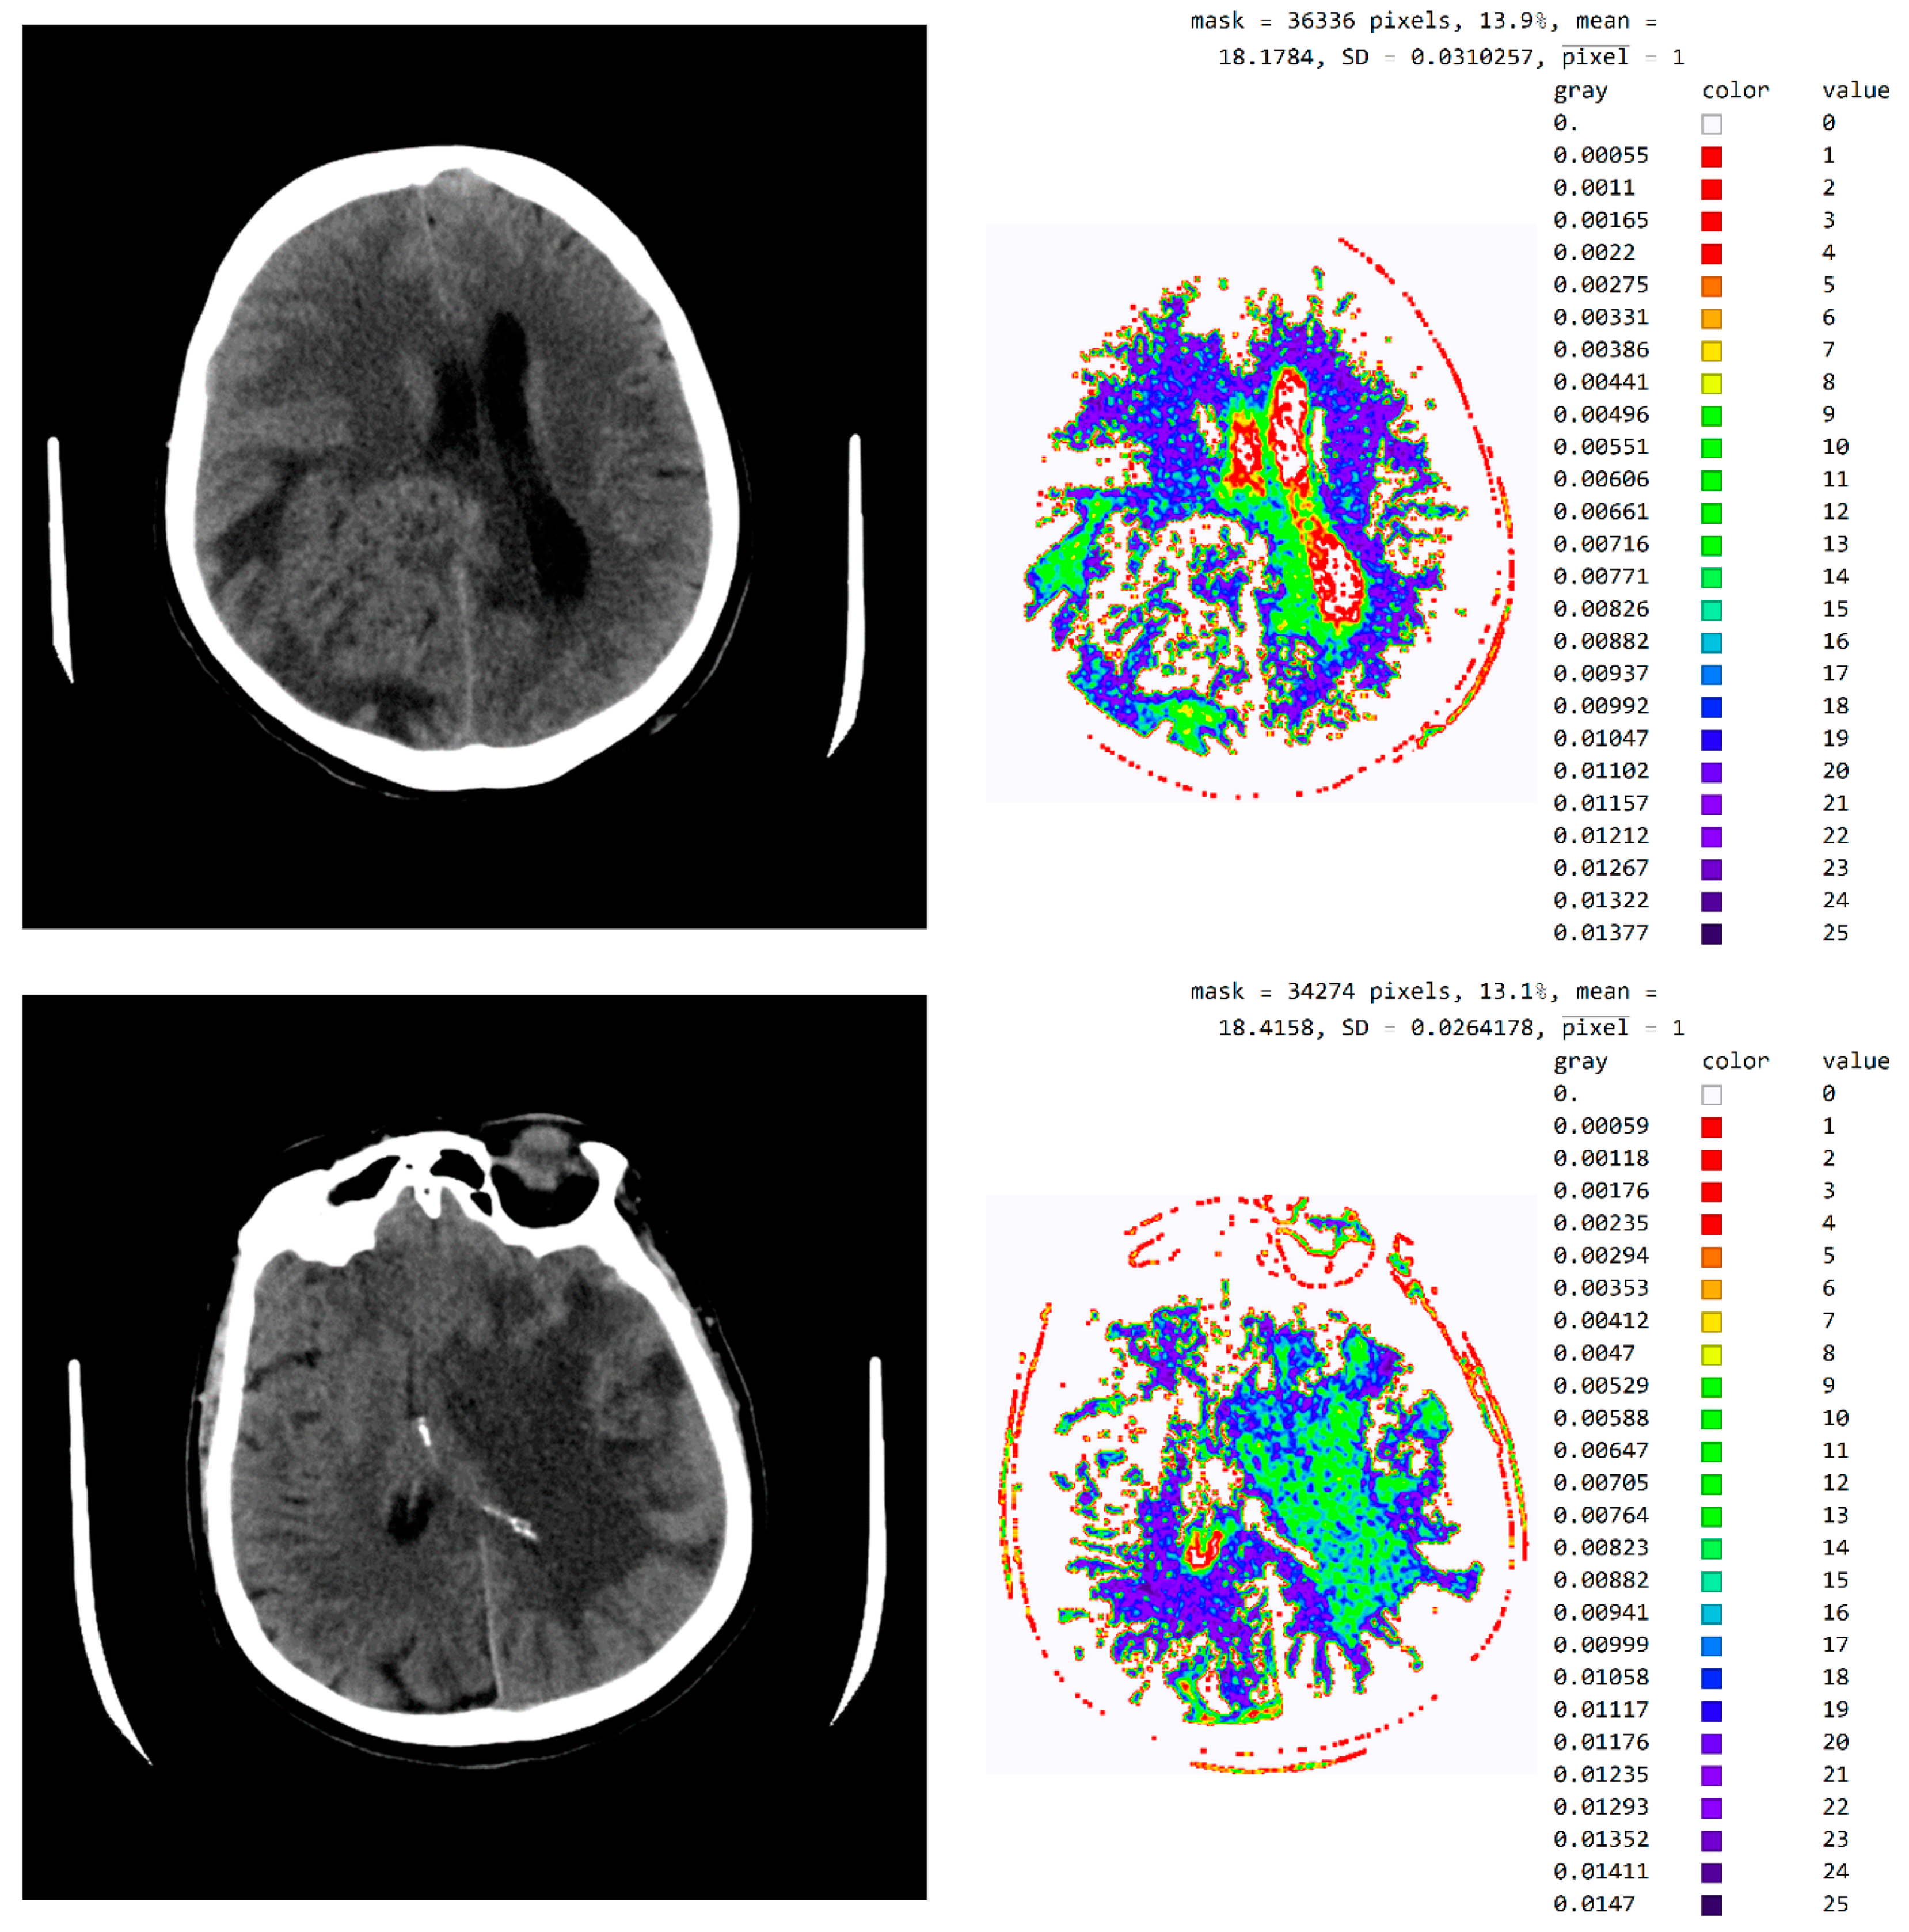

Figure A3 in Appendix A provides a tabular presentation of the various ranges of values and color maps in SVMI processing for different diagnosed brain diseases.

Figure A3.

SVMI processing of non-contrast MDCT image. (a) Non-contrast MDCT image and (b) Smart Visualization of Medical Images SVMI.